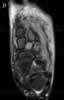

The T2-weighted MRI scan reveals increased signalin the second cuneiform body with breakthrough into thesurrounding dorsal tissue (Figure 6, A and B). The scanconfirms the diagnosis of osteomyelitis.

Arrangements are made for the patient to undergoincision and drainage of the left foot. During the procedure,15 mL of pus is removed; blood cultures growStaphylococcus aureus, which is sensitive to oxacillin. Antibiotictherapy is adjusted accordingly.

Several imaging techniques aid in the diagnosticworkup of a patient with symptoms of persistent or worseningcellulitis. Although plain x-ray films may reveal anunderlying foreign body or chronic osteomyelitis, they arenot an effective means of evaluating early signs of septicarthritis or osteomyelitis. Nuclear bone scanning, however,may show early evidence of these disorders-usually within24 to 48 hours of their onset. This test may help establishthe diagnosis if signs and symptoms are inconclusive.CT scanning may detect bone destruction secondary to infection,but it is not as sensitive in detecting early signs ofosteomyelitis compared with the bone scan or MRI.MRI offers the best means of visualizing bones,cartilage, and soft tissue structures without ionizing radiation.In osteomyelitis and septic arthritis, a T2-weightedMRI image shows enhanced signals of early inflammationin the periosteum and marrow and in synovium,respectively.